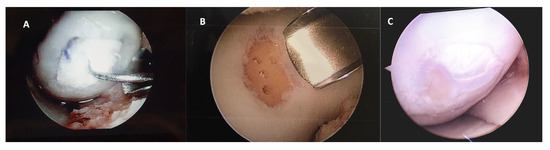

After 12 months of follow-up, a small number of patients required a new second-look arthroscopy, during which the integrity of the graft was verified to assess the degree of defect, fill, graft integration to the adjacent normal articular surface, and gross appearance of the graft surface. We were unable to observe a case without integration into adjacent normal articular tissue (Figure 4).

Figure 4.

Representative macroscopic view of the cartilaginous repair tissue within the circular full-thickness cartilage defects and adjacent cartilage during surgery for (A) the HA 3-D scaffold and (B) the microfractures groups. Letter (C) is the macroscopic view of the second-look arthroscopy (after 12 months) for the patient treated with HA 3-D scaffold with the graft completely integrated to the normal adjacent articular surface, without evident filling defects.